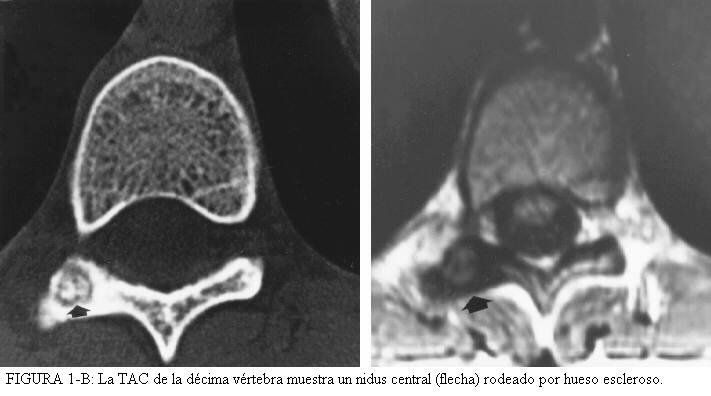

- osteoma osteoide de la columna: (figura 1-A y 1-B)

- localizado más a menudo  en los elementos posteriores;

- puede no producir una reacción ósea;

- puede provocar escoliosis secundaria al dolor;

Hay que cuatro características diagnósticas que ofrece el osteoma osteoide. La lesión es redonda u ovoide y normalmente es menor de un centímetro de diámetro. El centro de la masa es homogéneamente densa, y hay una zona delgada, de uno a dos-milímetros radiolucente periférica. En un estudio, aproximadamente el 50% de 448 osteomas osteoide mostró todos estos rasgos. Los huesos normalmente involucrados eran el fémur (135 de 448, 30%), la tibia (121 de 448, 27 %), el húmero (cuarenta y cinco de 448, 10%), la columna (treinta y uno de 448, 7%), y el talus (dieciocho de 448, 4%). En los huesos largos, la lesión es normalmente intracortical; en la columna, involucra normalmente, los elementos posteriores ( Fig. 1A y Fig. 1B). El osteoma osteoide del talus normalmente se encuentra más en el cuello que en el cuerpo.

TAC:

El nidus se localiza mejor con  la CT, dicen los radiólogos, para el diagnóstico diferencial.

Los cortes deben ser de 1-2 mm para visualizar el nidus

Deben ajustarse las escenas de la ventana del escáner de CT para que la reacción densa alrededor de la lesión no disimule el pequeño nidus de densidad baja.

RM:

Generalmente la RM tiene un papel pequeño para el diagnóstico, porque el hueso tiene una señal baja.

A pesar de esto, puede usarse para confirmar el diagnóstico o ayudar a descartar otras lesiones.

Ver imagen